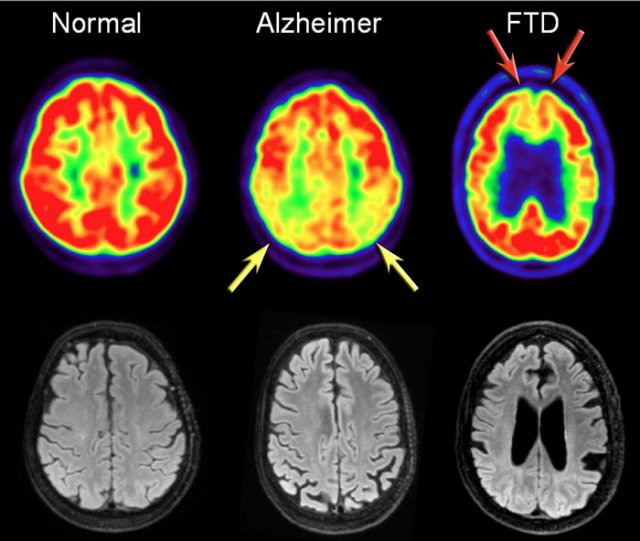

FDG-PET

In addition to clinical findings, CSF and MRI, PET-imaging is useful in diagnosing AD.

In AD FDG-PET can show hypometabolism in the temporoparietal regions and/or the posterior cingulum.

This may help differentiate AD from FTD, which shows frontal hypometabolism on FDG-PET.

The images show FDG-PET and axial FLAIR images of a normal subject and of patients with AD and FTD.

FDG-PET (top row) and axial FLAIR images of a normal subject and of AD and FTD patients.

In AD there is a decreased metabolism of the parietal lobes (yellow arrows), whereas in FTD, there is frontal hypometablism (red arrows).